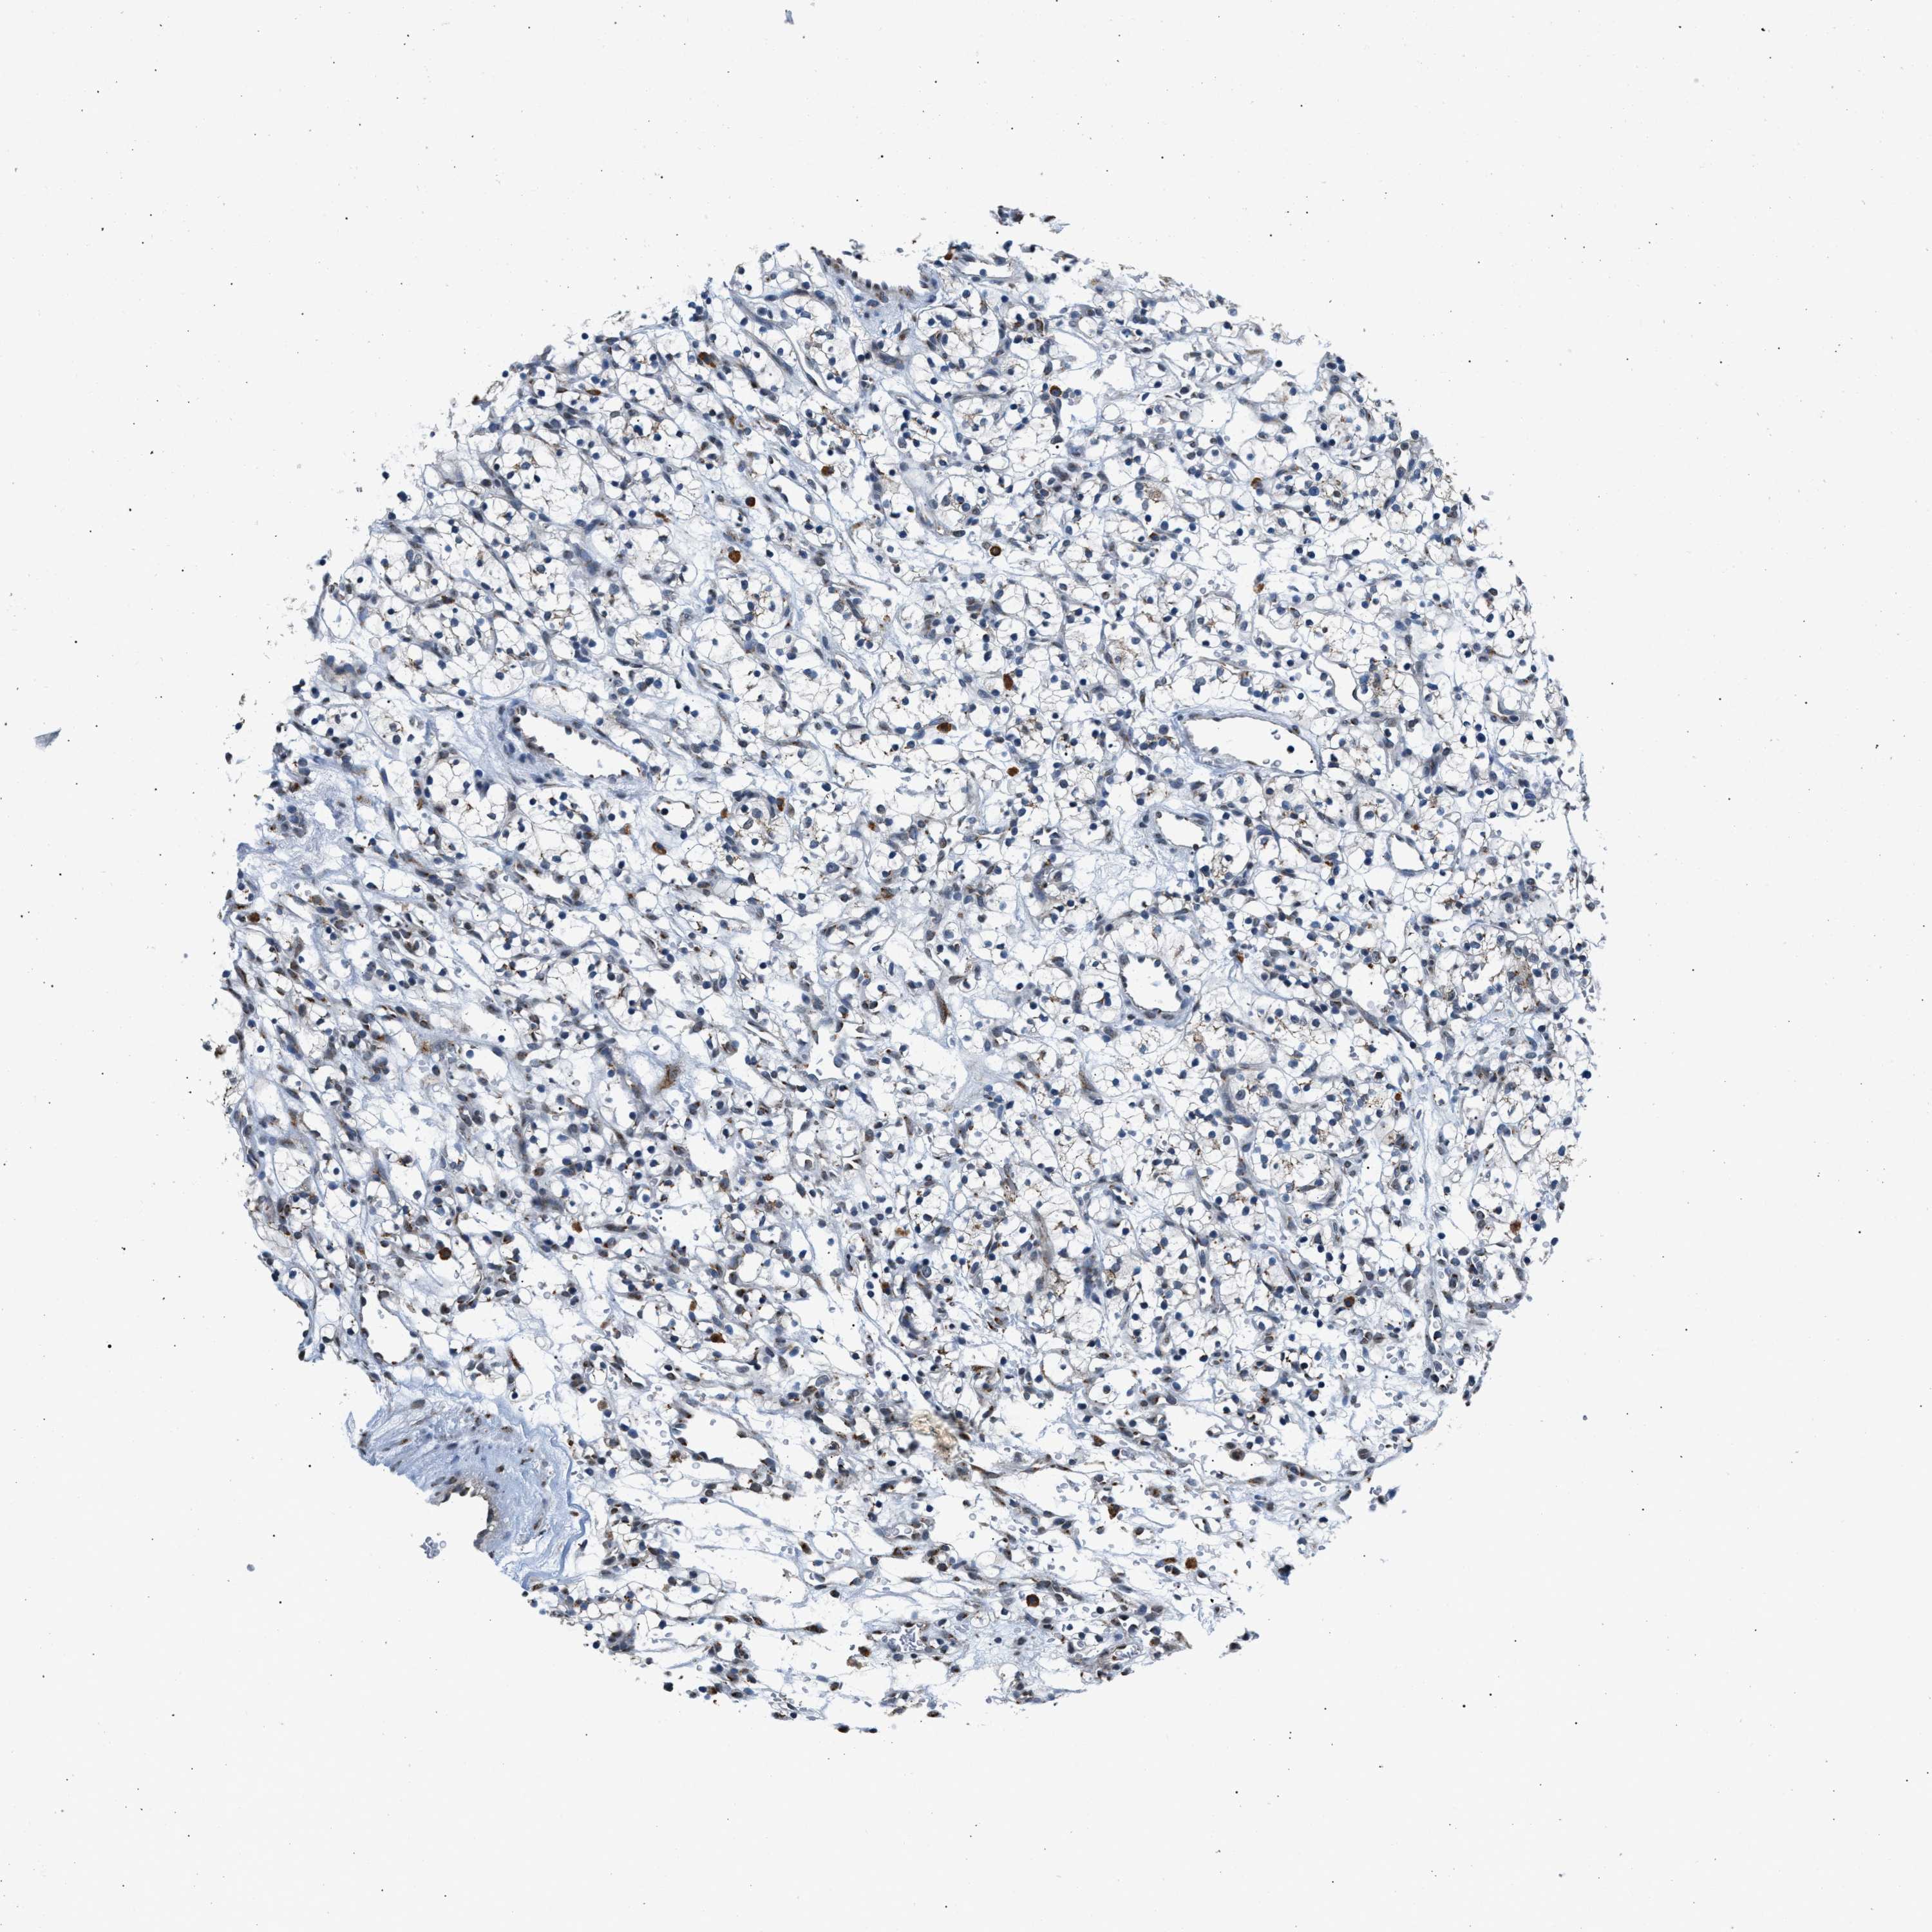

TCGA RNA samplesi

RNA-seq data is reported as average FPKM (number Fragments Per Kilobase of exon per Million reads), generated by the The Cancer Genome Atlas (TCGA) .

Normal distribution across the dataset is visualized with box plots, shown as median and 25th and 75th percentiles. Points are displayed as outliers if they are above or below 1.5 times the interquartile range. FPKM values of the individual samples are presented next to the box plot.

Average pTPM 1.2